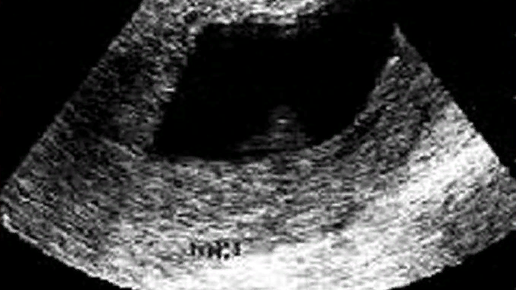

У меня была 6 неделя беременности. При первом посещении больницы, гениколог сказал что все хорошо, беременность очень хорошая .У меня был ранний токсикоз, каждый день меня тошнило, абсолютно на все, я даже не могла нормально почистить зубы. Но через две недели он закончился. С работы пришлось отпросится на этот период за свой счёт т.к больничный мне не дали. Цитирую врача гинеколога и терапевта: "беременность ведь не болезнь"...